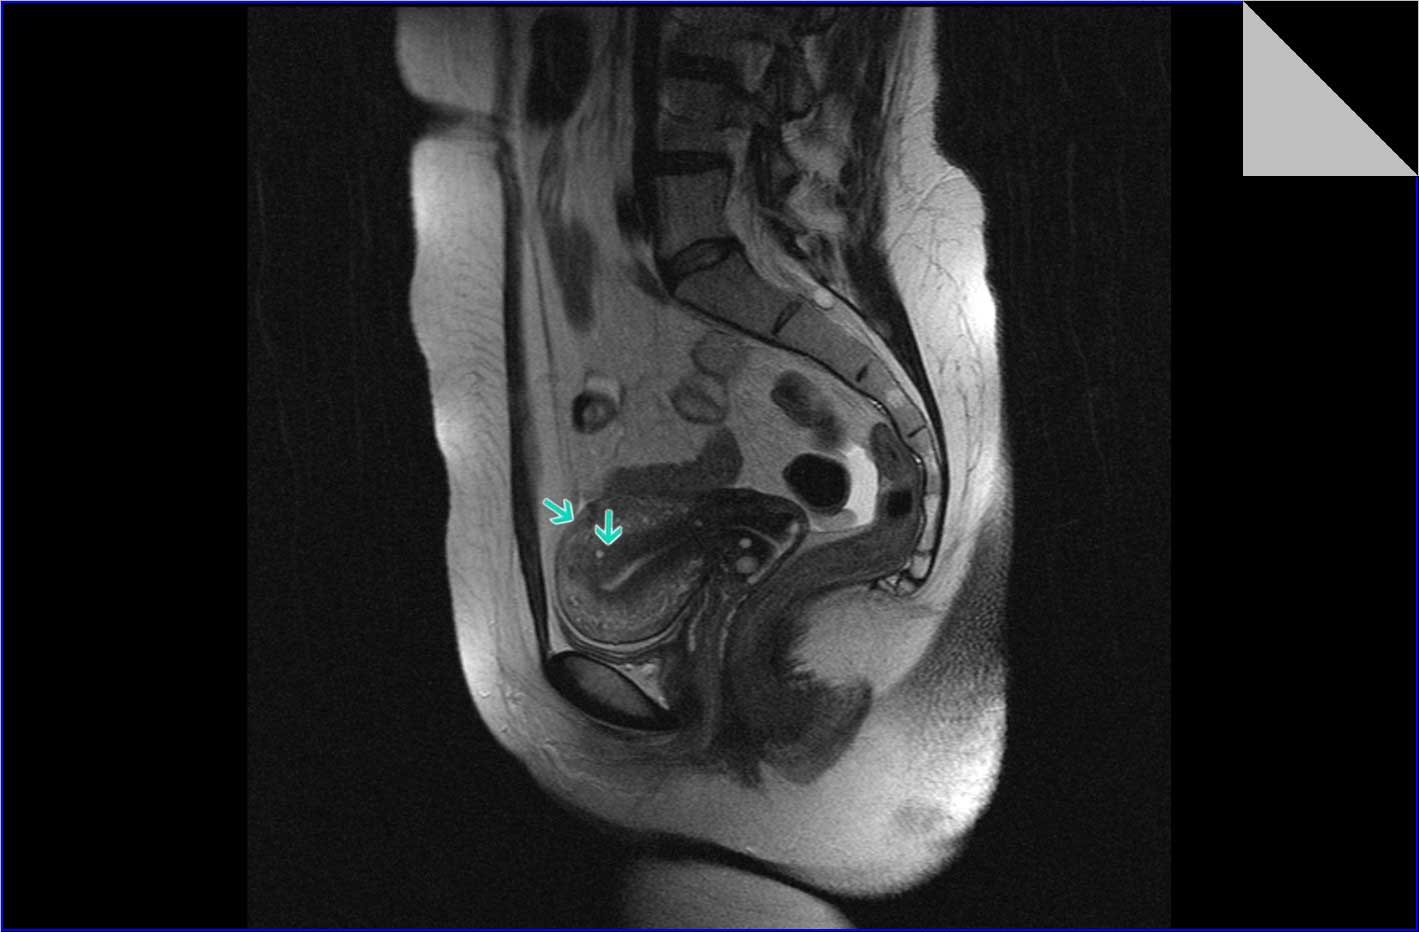

Магнитно-резонансная томография (МРТ) малого таза у женщин является важным методом диагностики различных заболеваний. На фотографиях МРТ можно увидеть органы малого таза, такие как матка, яичники, мочевой пузырь, прямая кишка и другие структуры.

Примеры фото МРТ малого таза у женщин

Ниже представлены примеры фотографий МРТ малого таза у женщин, позволяющие увидеть, как выглядят снимки и какие изменения могут быть обнаружены специалистами.